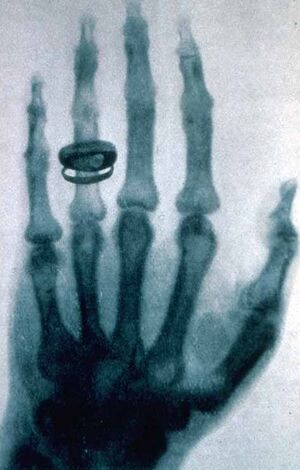

His hand was one of the first to be x-rayed, by his friend Wilhelm Röntgen.[3]

X-ray of Kölliker's hand, made by Röntgen on 23 Jan 1896